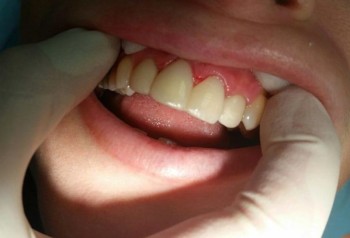

Писарская Елена Николаевна: портфолио (2)